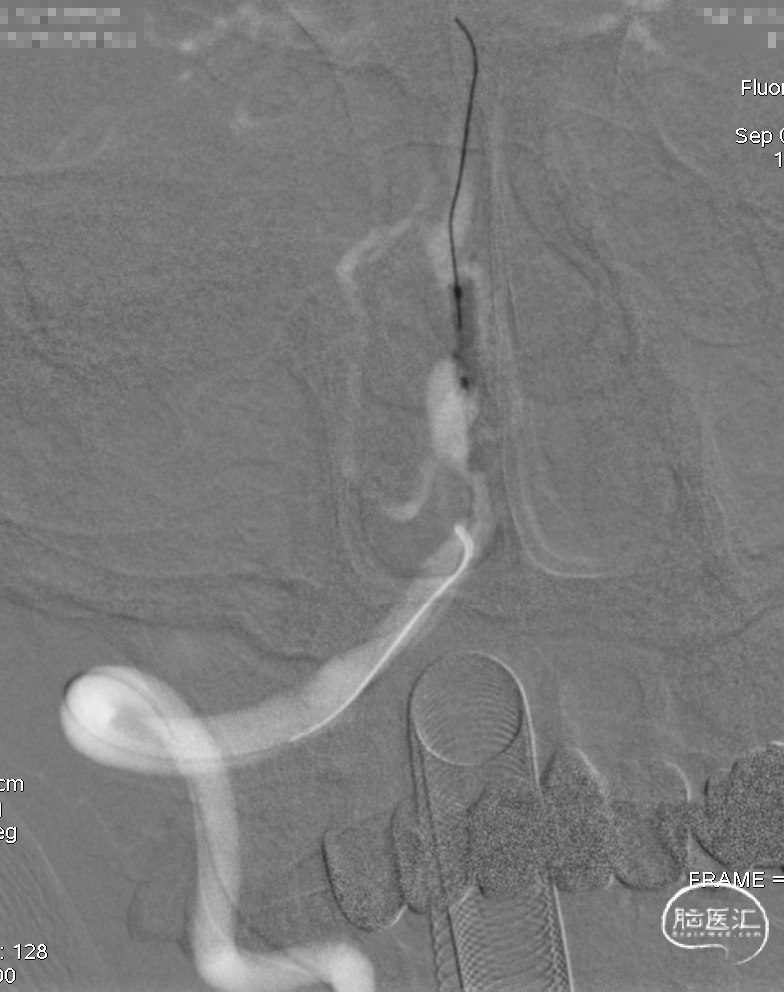

术后即刻DSA。

术后即刻稀释造影:“拉直”可见支架贴壁良好。